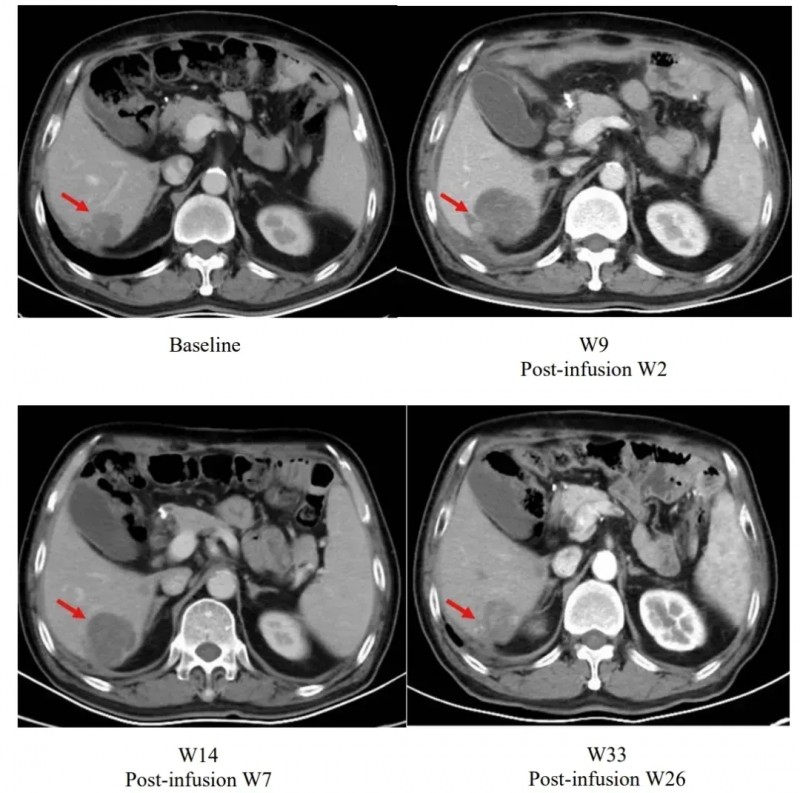

除此之外,2025年美国临床肿瘤学会(ASCO)大会上,其2期临床试验(CT041-ST-01)重磅数据更新,一个典型案例引发关注:患者输注satri-cel后第2周肝脏病灶虽较基线增大,但后续随访中持续缩小,至第26周已小于基线水平,直观印证了疗法的持续抗肿瘤活性。

▲图源“The Lancet”,版权归原作者所有,如无意中侵犯了知识产权,请联系我们删除